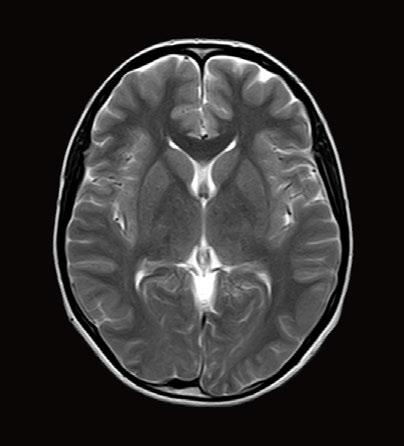

Fig 1: Next generation MRI is being used to gather data on brain tissue volumes Dr. Steve McNally

From this season at Manchester United Football Club, we have started to gather data by using MRI (see fig 1) to measure volumes of brain tissue in specific areas, to monitor for a decrease in volumes over time. If the volumes become unusual or deviate from the norms that we would expect, it may help us identify early changes of CTE that need closer monitoring. This is a new, long-term data gathering study in our cohort of players that has been facilitated with the new next generation MRI3 now in place at our medical centre.

MRI is also an excellent choice of tool for the diagnosing and monitoring of Chronic Traumatic Encephalopathy (CTE), the result of repetitive brain trauma from blows to the head and repeated episodes of concussion, which in football may have come from player contact or heading the ball. It is a hot topic in all contact sports such as boxing, rugby and martial arts and follows research at the University of California, Los Angeles (UCLA) using MRI as the option to explore CTE without any dose implications to patients2

32 // VISIONS SPECIAL